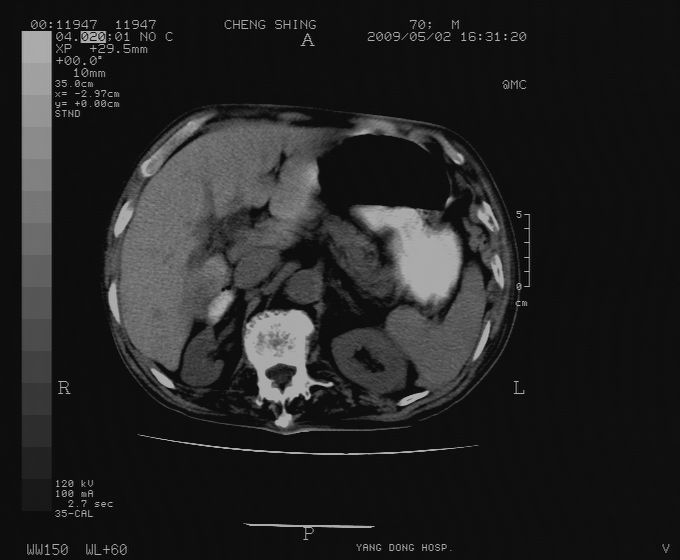

标题: CT19743:男70岁,肺部疾病入院,B超发现肝右叶占位,CT [打印本页]

标题: CT19743:男70岁,肺部疾病入院,B超发现肝右叶占位,CT

肝表面塌陷,病灶周围有子灶,前面较大子灶强化符合肝癌表现,考虑肝癌肝转移可能性大.

1.考虑肝癌肝转移

2.两侧胸水,左下肺不张!

1)考虑肝癌并肝内转移。2)少量腹水。3)双侧胸腔积液。

1)考虑肝癌并肝内转移。2)少量腹水及双侧胸腔积液。3)椎体退变。